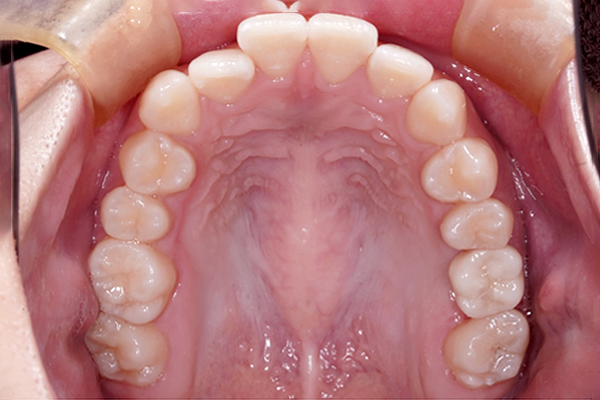

上の歯の比較(咬合面)

歯槽堤温存術の症例

抜歯時に歯槽堤温存術(リッジプリザベーション)を行うことが出来たので、インプラント治療時に大きな骨造成を行わなくても治療を行うことが出来ました。治療期間は8ヶ月でした。

今後は、長期的にインプラントを安定させることができる様にメインテナンスを行なっていきましょう。